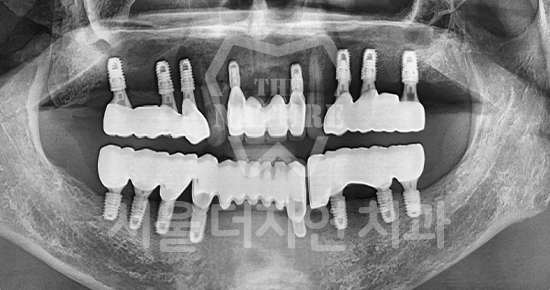

Various Implant Treatment Cases

#Full Mouth Implants

• BEFORE: 2022.12.15

• AFTER: 2023.02.23

#Sinus Lift

• BEFORE: 2021.02.01

• AFTER: 2021.05.13

#Maxillary Bone Grafting

• BEFORE: 2021.11.02

• AFTER: 2022.01.19

Treatment outcomes may vary by patient,

and side effects may occur. These images were taken under the same conditions,

and were published with the patient's consent.